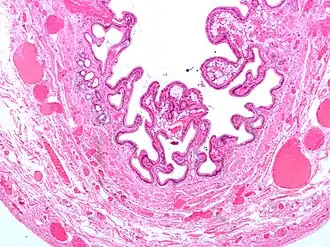

| Micrografia da colesterolose da vesícula biliar. Mancha de H&E. | |

Na patologia cirúrgica, vesícula biliar de morango, mais formalmente colesterolose da vesícula biliar e colesterolose de vesícula biliar, é uma alteração na parede da vesícula biliar devido ao excesso de colesterol.[1]

O nome vesícula biliar de morango vem da aparência tipicamente pontilhada da superfície da mucosa, em um exame grosseiro, que se assemelha à aparência de um morango.

Colesterolose da vesícula biliar (Imagem grosseira). Micrografia da colesterolose da vesícula biliar.

Micrografia da colesterolose da vesícula biliar. Micrografia da colesterolose da vesícula biliar.

Micrografia da colesterolose da vesícula biliar. Micrografia da colesterolose da vesícula biliar.

Micrografia da colesterolose da vesícula biliar.